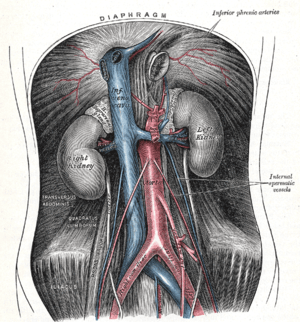

The abdominal aorta and its branches (internal spermatic vessels labeled at right) | |

They are two slender vessels of considerable length, and arise from the front of the aorta a little below the renal arteries.

Each passes obliquely downward and lateralward behind the peritoneum, resting on the Psoas major, the right lying in front of the inferior vena cava and behind the middle colic and ileocolic arteries and the terminal part of the ileum, the left behind the left colic and sigmoid arteries and the iliac colon.